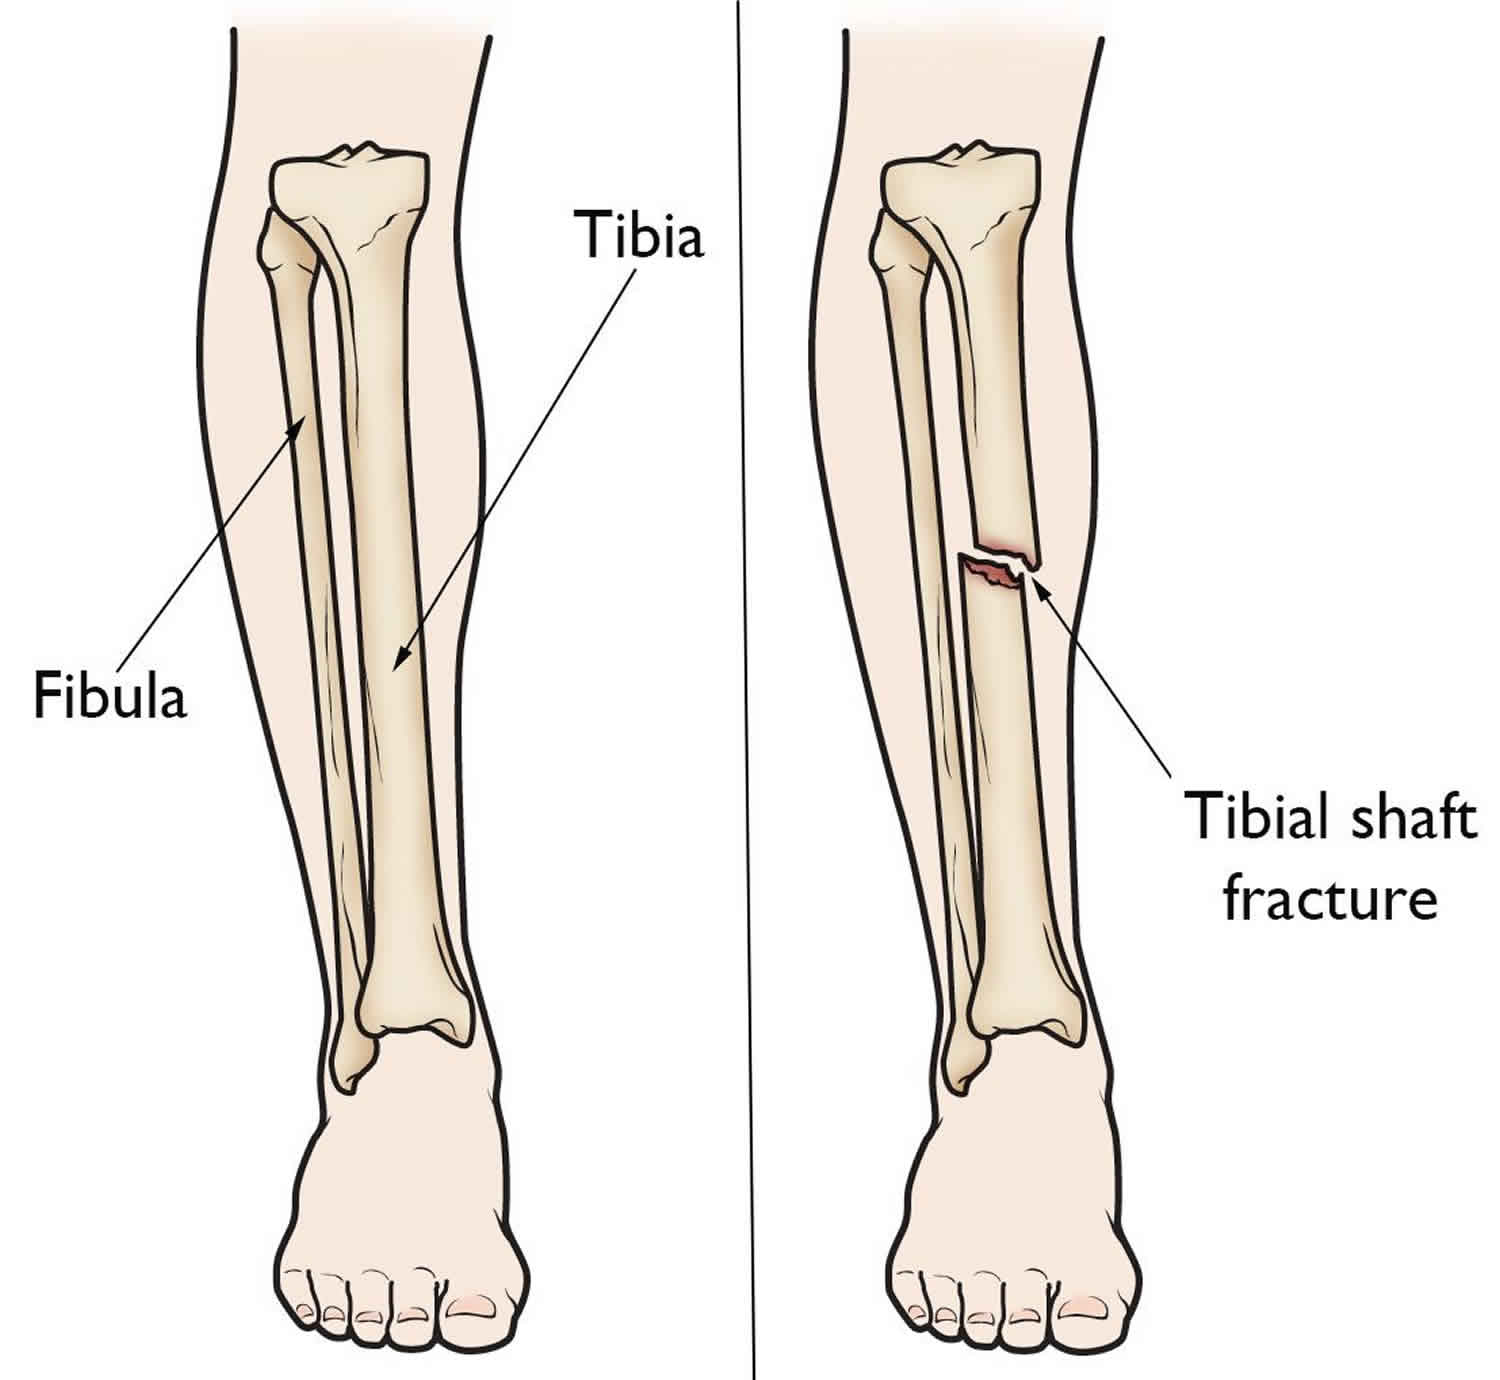

12. Rhinelander FW. Tibial blood supply in relation to fracture healing. Clin Orthop Relat Res. 1974:34–81. [PubMed] [Google Scholar]

21. Richards RR, Schemitsch EH. Effect of muscle flap coverage on bone blood flow following devascularization of a segment of tibia: an experimental investigation in the dog. J Orthop Res. 1989;7:550–8. [PubMed] [Google Scholar]

22. Richards RR, McKee MD, Paitich CB, Anderson GI, Bertoia JT.

A comparison of the effects of skin coverage and muscle flap coverage on the early strength of union at the site of osteotomy after devascularization of a segment of canine tibia. J Bone Joint Surg Am. 1991;73:1323–30. [PubMed] [Google Scholar]

23. Richards RR, Orsini EC, Mahoney JL, Verschuren R. The influence of muscle flap coverage on the repair of devascularized tibial cortex: an experimental investigation in the dog. Plast Reconstr Surg. 1987;79:946–58. [PubMed] [Google Scholar]

120. Papakostidis C, Kanakaris NK, Pretel J, Faour O, Morell DJ, Giannoudis PV. Prevalence of complications of open tibial shaft fractures stratified as per the Gustilo–Anderson classification. Injury.

2011;42:1408–15. [PubMed] [Google Scholar]

121. Giannoudis PV, Harwood PJ, Kontakis G, et al. Longterm quality of life in trauma patients following the full spectrum of tibial injury (fasciotomy, closed fracture, grade IIIB/IIIC open fracture and amputation) Injury. 2009;40:213–9. [PubMed] [Google Scholar]

124. Gopal S, Majumder S, Batchelor AG, Knight SL, De Boer P, Smith RM. Fix and flap: the radical orthopaedic and plastic treatment of severe open fractures of the tibia. J Bone Joint Surg Br. 2000;82:959–66. [PubMed] [Google Scholar]